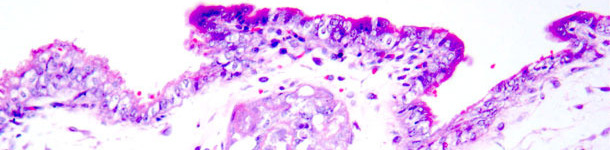

Ryc. 1 - Martwica skrzepowa trofoblastu. Barwienie hematoksyliną i eozyną.

Ryc. 2 - Immunohistochemiczne barwienie antygenu PCV2b w zmianach martwiczych trofoblastu (kolor brązowy).

Chromogen: diaminobenzydyna; barwienie kontrastowe: hematoksylina.

Pierwsze doświadczenie przeprowadzno na 9 konwencjonalnych loszkach podzielonych na dwie grupy: sześciu inseminowanych nasieniem zanieczyszczonym PCV2 i trzech inseminowanych nasieniem bez PCV2. U loszek o najniższym poziomie przeciwciał przed infekcją, doszło do wzrostu ich poziomu w następstwie inseminacji zakażonym nasieniem, a także stwierdzono u nich płody dodatnie w kierunku PCV2. W przypadku jednego łożyska stwierdzono ogniska łagodnej martwicy nabłonka kosmówki oraz dodatni wynik barwienia antygenu PCV2 techniką immunohistochemii. Uzyskane wyniki wskazują, że loszki serologicznie dodatnie w kierunku PCV2 mogą ulec zakażeniu PCV2 przez inseminację, niski poziom przeciwciał u takich zwierząt zwiększa prawdopodobieństwo infekcji płodu, zmiany w łożysku wywołane przez PCV2 mogą wskazywać na ich rolę w zaburzeniach płodowych oraz, że zakażenie PCV2 w okresie inseminacji może skutkować zakażeniem zarodków.